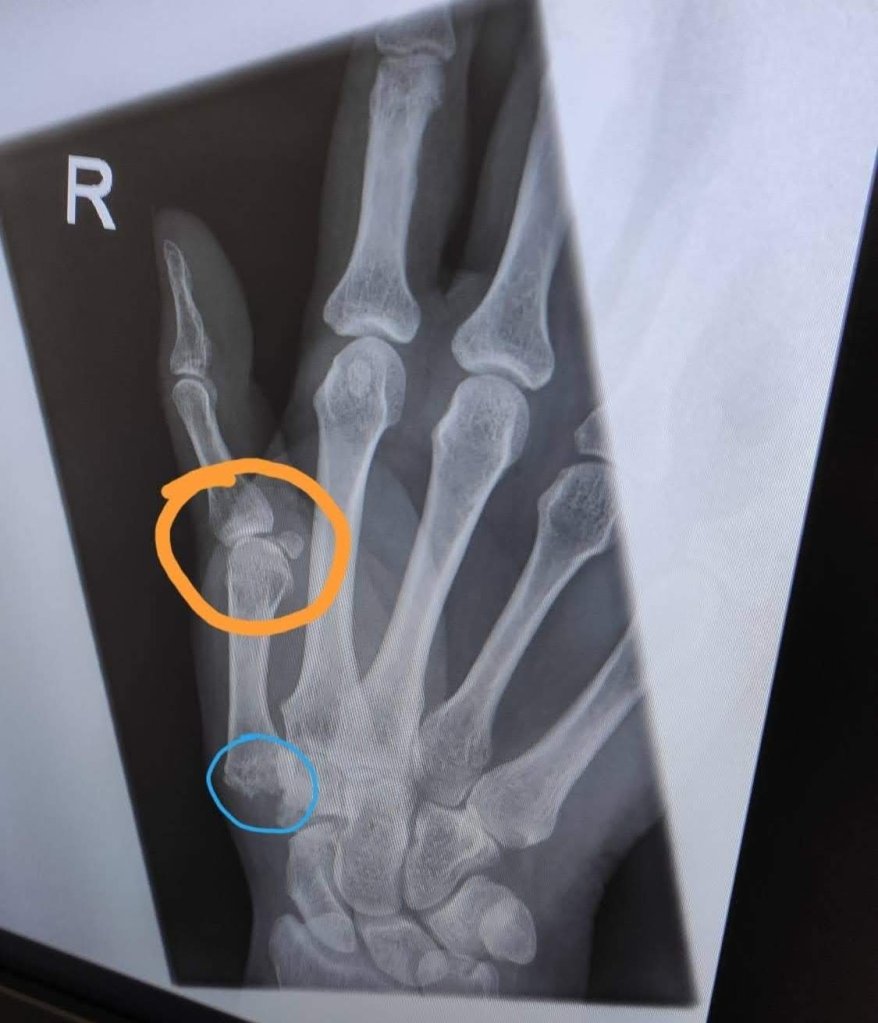

As you can see it’s collapsed and not in a good position, unlike the other one, hence the change in surgery being offered, for this one we are doing a joint replacement instead of fusion. We discussed the MCP joint maybe needing to be fused. She also wants another surgeon with her. So to coordinate may take a bit longer, possible a 3 month wait. But this actually helps me a bit, gives me time to have the Psoas Hip Steroid injection, and intense hydro before taking my dominant hand out of action.